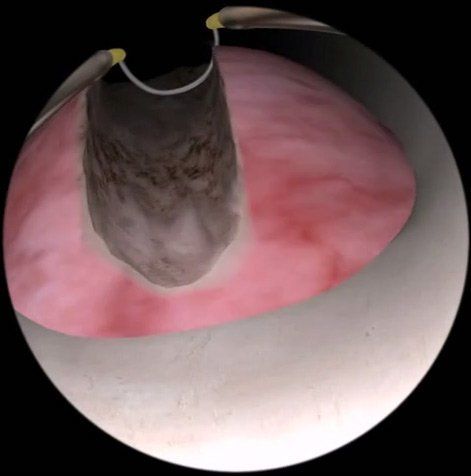

Surgical Treatment